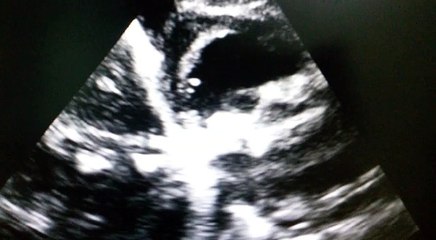

Mitral Valve Calcification and Homeopathy lecture by Doctor Abdul Haye Sialkot,Pakistan

"Mitral Valve Calcification & HOMEOPATHY", lecture No.5, by Dr Abdul Haye SIALKOT ,PAKISTAN.br 00923158095060br 00923338625356br dr.abdulhaye@gmail.combr br 1. #MitralValveCalcificationbr 2. #Homeopathybr 3. #HeartHealthbr 4. #CardiacCarebr 5. #MitralValvebr 6. #CalcificationTreatmentbr 7. #HomeopathicTreatmentbr 8. #CardiovascularHealthbr 9. #HeartDiseasebr 10. #HolisticHealingbr 11. #DoctorAbdulHayebr 12. #HomeopathyForHeartbr 13. #HeartConditionsbr 14. #HealthyHeartbr 15.